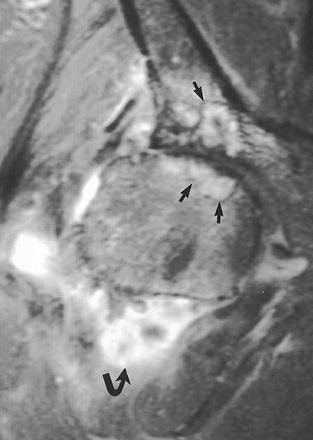

| Rapidly destructive hip osteoarthritis in 68-year-old woman with right-sided hip pain. Coronal fat-suppressed gadolinium-enhanced T1-weighted MR image (TR/TE, 720/20) obtained six months after onset of symptoms shows frank synovitis (curved arrow). Note presence of cystlike subchondral defects (straight arrows) at weight-bearing surfaces of femoral head and acetabulum. Boutry N, Paul C, Leroy X, Fredoux D, Migaud H, Cotton A, "Rapidly Destructive Osteoarthritis of the Hip: MR Imaging Findings" (AJR 2002; 179:657-663). |

For JSN assessment, MRI can reveal meniscal degeneration, which is a key to accurate JSN measurements. A study by radiologists at the Boston VA Medical Center showed that increasing meniscal subluxation on MRI correlated strongly with the severity of JSN on plain x-ray in the symptomatic knee (Osteoarthritis and Cartilage, November 1999, Vol. 7:6, pp. 526-532).

In keeping with the new clinical approach that stresses OA tracking, Cibere acknowledged that MRI can detect degenerative changes at an earlier stage than x-ray. But as is usually the case with the modality, the high cost of MR is a limiting factor for its use in OA, she said.